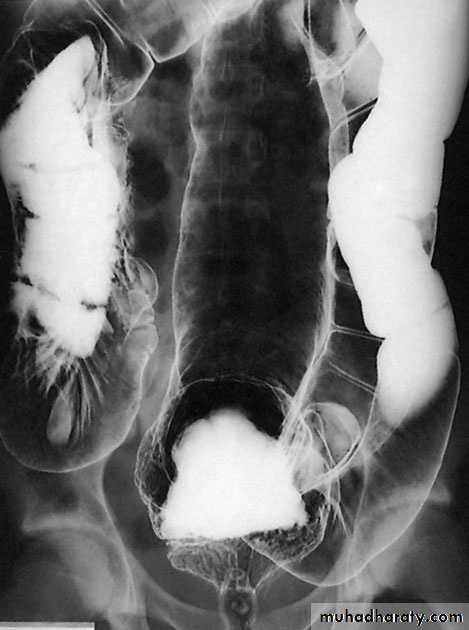

InvestigationImagingAs there is an enlarged rectum, often with distension of the colon over a variable length, a radiograph should be taken without prior bowel preparation, using a small quantity of water-soluble contrast to prevent barium impaction. There is usually gross faecal loading of the enlarged rectum and colon and, when a contrast examination is carried out, the width of the colon measured at the pelvic brim is usually more than 6.5 cm.

DiverticulosisIt is important to distinguish between diverticulosis, which maybe asymptomatic, and clinical diverticular disease in which thediverticula are causing symptoms. On histological investigation,the diverticulum consists of a protrusion of mucous membranescovered with peritoneum. There is thickening of the circularmuscle fibres of the intestine, which develops saw-tooth appearance on barium enema